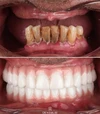

عدسات الأسنان (لامينا)

تبييض الأسنان